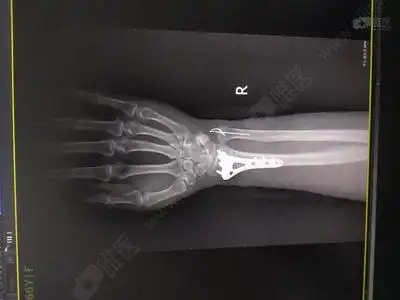

男孩,9岁,右桡骨远端骨折

右侧桡骨远端骨折怎么治疗

桡骨远端骨折手法复位前后对比 - 好大夫在线

郴州人民医院x光,诊断结果,右手桡骨远端骨折.

右尺桡骨远端骨折1例

右尺桡骨远端骨折中医表姐手法复位治疗记二图片